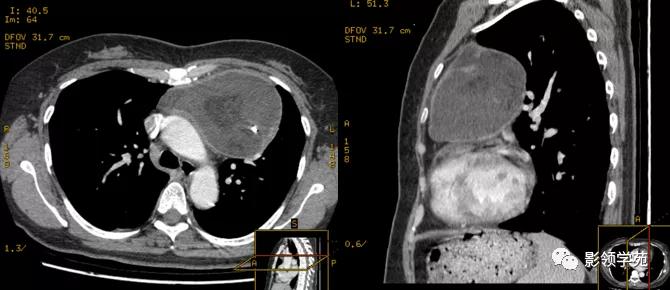

体检发现纵隔肿块

密度均匀,强化均匀

恶性胸腺瘤

穿刺证实恶性胸腺瘤,伴有纵隔淋巴结肿大